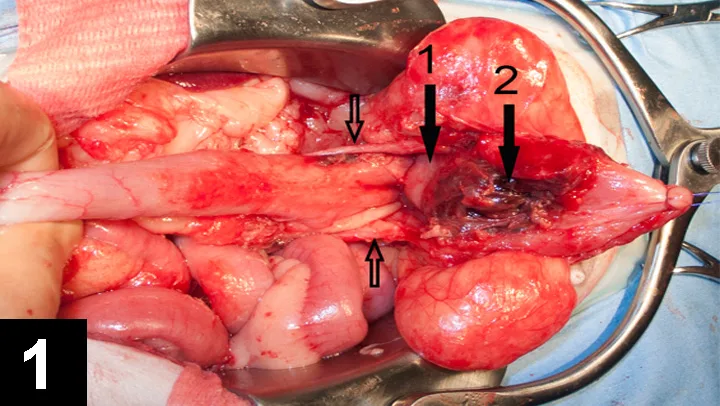

For various reasons, probably including time constraints, OVH is often performed through an as-small-as-possible abdominal incision, whether a ventral midline or flank approach is used, that is located to attempt to allow visualization of both the ovaries and the cervix but is optimal for neither; this can result in relatively poor exposure. Significant traction is required to reach the uterine body, and excessive traction on the uterus has been associated with rupture of uterine vessels and hemorrhage16 and is unnecessarily traumatic. Often, the cervix cannot be reached and identified when using a small incision approach; the uterus is, therefore, ligated and sectioned either without precise visual control, which exposes the patient to complications (Figure 1), or too cranially, leaving a significant portion or all of the uterine body (Figure 2). Such an incomplete resection is unlikely to cause problems but somewhat negates the putative advantages of OVH. This difficulty in reaching the cervix may be even greater with a flank approach,10,17 requiring considerable retraction of the abdominal wound, which may contribute to more postoperative pain than would a ventral midline approach.18

Figure 1

Partial bladder necrosis from vascular compromise after ovariohysterectomy (white arrow, uterine stump; yellow arrow, necrotic portion of the bladder; black arrows, ureters) in a dog